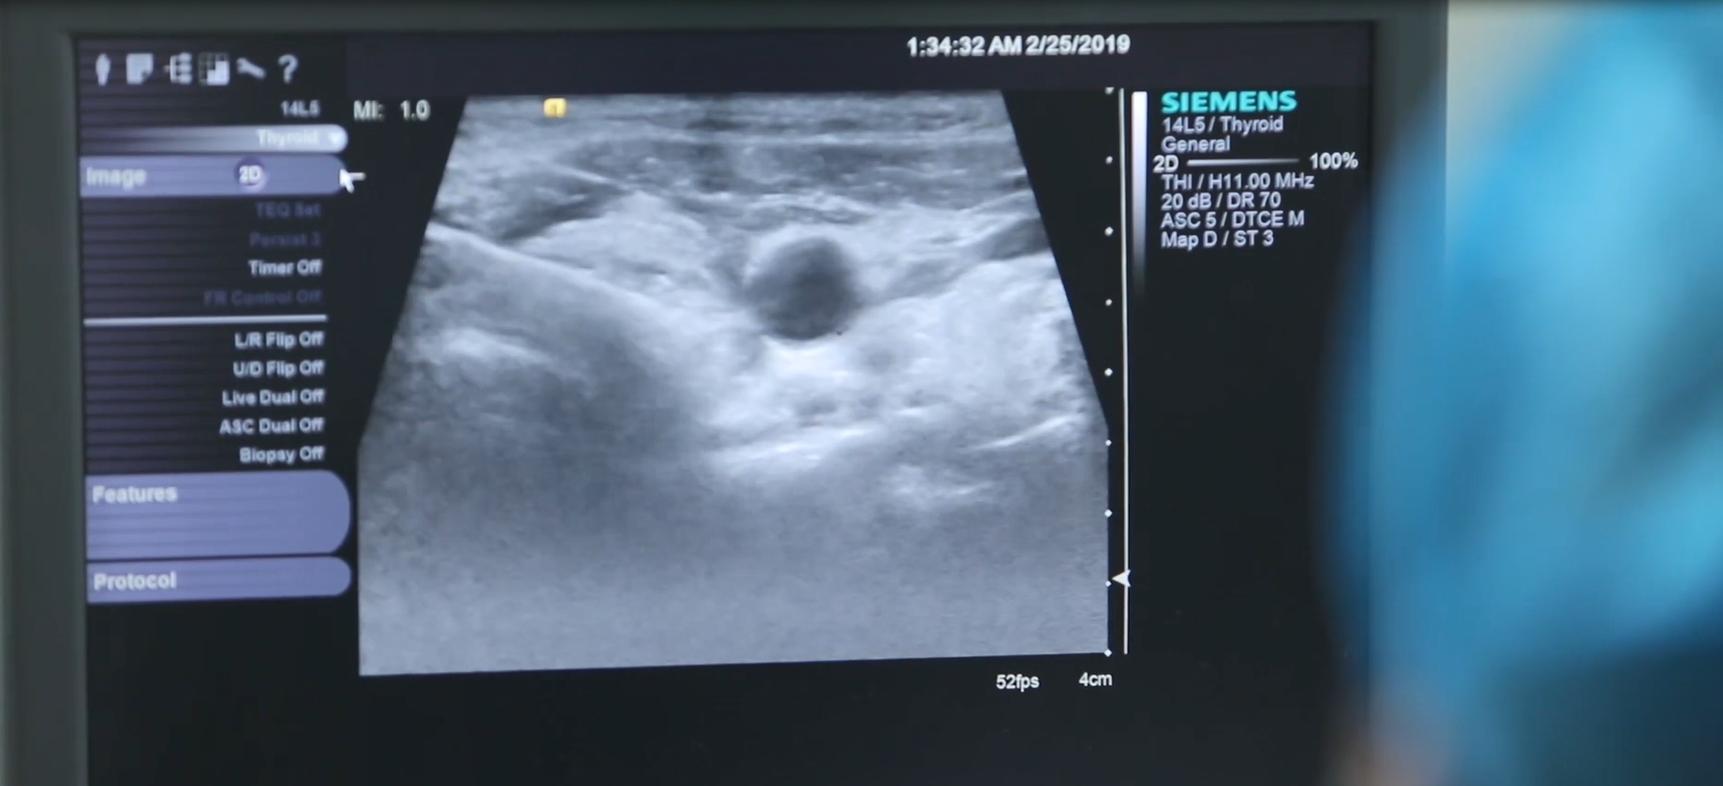

四维弹性成像结果出来,能看到结节倒是不大,性质也比较好,大概率是良性结节,如果庾女士想做也可以做,不用开刀,做微创消融就可以了。